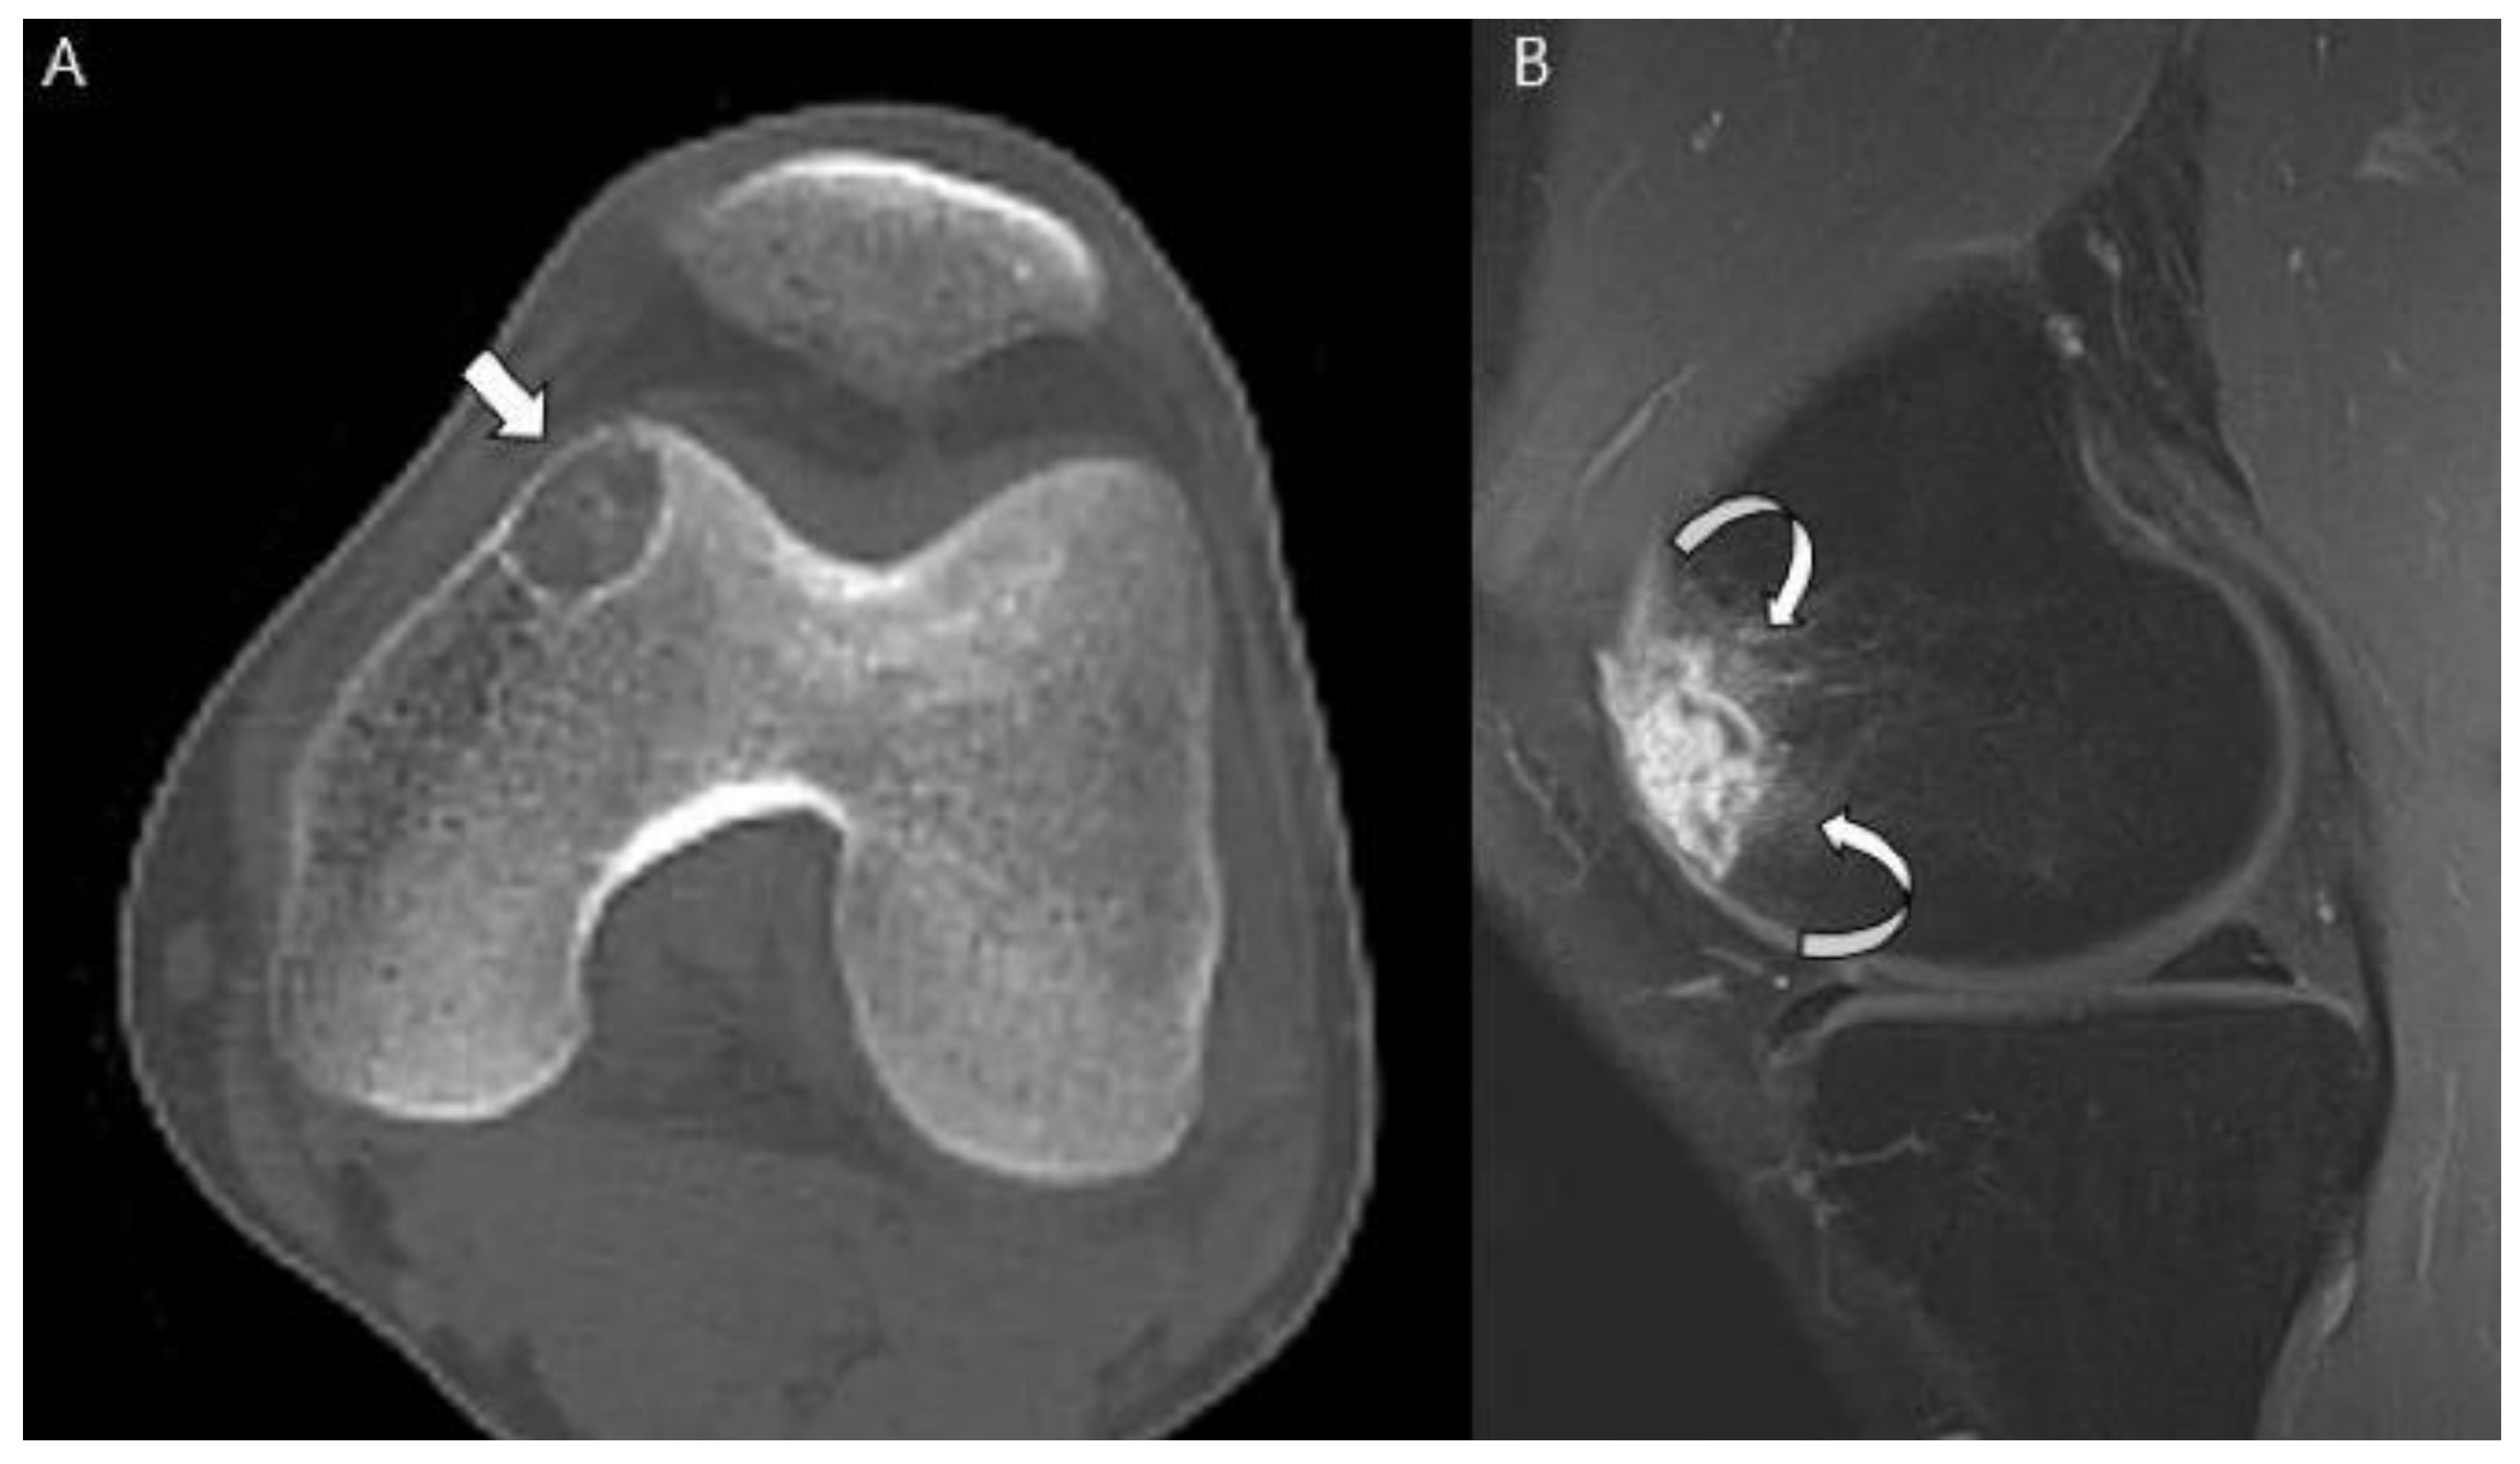

Clear cell chondrosarcomas are low-grade variants characterized by an epiphyseal location in long bones [45]. On histological analysis, these lesions have numerous cells with abundant clear vacuolated cytoplasm [1,5]. Patients are most commonly affected in the 3rd to 5th decades of life [1]. Long bones are affected in 85–90% of cases with the proximal femur (68%) and proximal humerus (23%) the most commonly involved long bones [45]. Radiographs reveal a predominantly lytic epiphyseal lesion with distinct sclerotic margins that simulate a benign lesion [5,45] (Figure 12). Matrix mineralization is not as frequently apparent in clear cell chondrosarcomas (approximately 30% of cases) as in conventional chondrosarcomas [46,47,48]. In approximately 30% of cases, mild bone expansion may be apparent, but soft tissue extension is rare (<10% of cases) [1,5]. Because of their epiphyseal location, clear cell chondrosarcomas can be difficult to distinguish from chondroblastomas [1]. Clinically, clear cell chondrosarcomas usually present one or two decades later than chondroblastomas [18]. On MRI, clear cell chondrosarcomas are heterogeneous due to areas of hemorrhage or cystic changes [45]. Peritumoral edema is unusual and always mild as opposed to that in chondroblastoma [45].

Figure 12.

Clear cell chondrosarcoma of the distal femur in a 31-year-old man. (A) Axial CT scan shows an osteolytic lesion with a thin sclerotic margin at the distal femur (arrow). (B) Sagittal T1-weighted enhanced image with fat suppression shows a heterogeneously enhancing lesion with mild peritumoral enhancement at the distal femoral epiphysis (curved arrows).